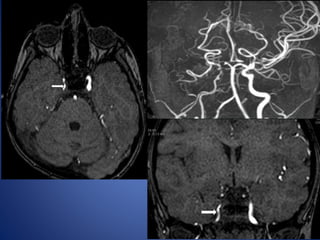

5 yrs male child with history of left sided focal seizures with secondary generalization

5 yrs malechild with history of left sided focal seizures with secondary generalization

• Stenosis/occlusion ofthe distal ICA • moyamoya vessels with signal voids in the basal ganglia • ischemia • infarction • atrophy, and ventriculomegaly. • Small abnormal net-like vessels proliferate giving "puff of smoke" appearance. • Contrast-enhanced T1WI - marked leptomeningeal enhancement along the cortical sulci (ivy sign). often show contrast stagnating in slow-flowing collateral vessels both in the brain parenchymal and over its surface. MR imaging

• 24.